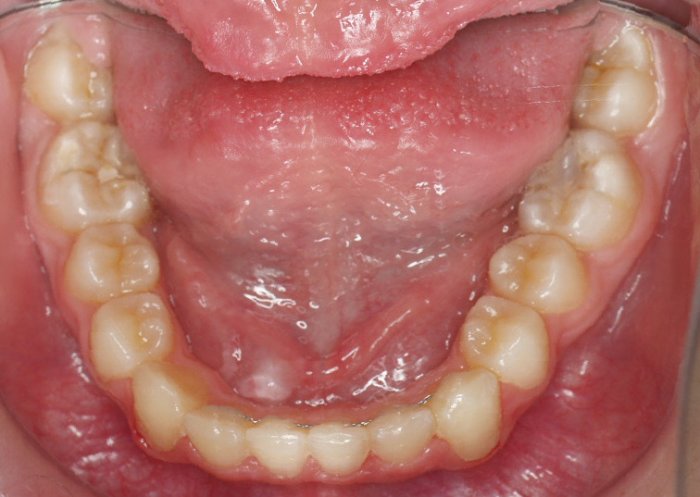

El paciente A.J. de 11 años, acude a nuestra consulta con apiñamiento maxilar importante. El canino lateral (12) está en mordida cruzada. Presenta una Clase II molar y canina, y la línea media está desviada. Se realizó un tratamiento con brackets autoligables metálicos de smartclip 022. La duración del tratamiento fue de 22 meses.

El paciente actualmente ha terminado el tratamiento con brackets y lleva una contención fija de 2-2 en maxilar y 3-3 en mandibular; para complementar también lleva una férula ESSIX durante la noche.

INICIO FINAL